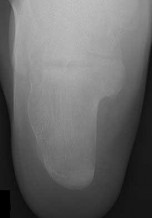

Figures 1a through 1c

Tarsal coalitions occur when primitive mesenchymal cells fail to differentiate and form the

normal articular separations between the tarsal bones of the hindfoot. Overall incidence is difficult to determine because many affected people are minimally symptomatic or asymptomatic. Symptomatic tarsal coalitions typically present in adolescents as a painful flatfoot; however, there are a number of possible presentations, and occasionally symptoms do not appear until adulthood. Most tarsal coalitions are between the calcaneus and the navicular (CN) and the talus and the calcaneus (TC). Although most TC coalitions are across the middle facet, posterior facet coalitions do occur. Plain radiographic evaluation of suspected tarsal coalition is the mainstay for diagnosis. However, coalitions can be bony or fibrous, and making the diagnosis can be difficult. The addition of CT images to distinguish bony definition and MR images to decipher soft tissue can aid in diagnostics. Bony coalitions appear as definite bony bridging between the bones, while fibrous coalitions are suspected when distortion of the bony anatomy is seen. Bony coalitions are best seen on the oblique view (CN) and Harris axial view (TC). There are a number of secondary signs such as the anteater (AE) sign (elongation of the anterior process of the calcaneus as it extends to the navicular as seen on the lateral view [CN]). talar beaking (traction spur of the talar neck thought to result from abnormal stresses as seen on the lateral view [both CN and TN]), and the “C” sign (a continuous cortical contour from the medial talus to the sustentaculum tali [ST]) as seen on the lateral view (TC). A number of newer signs are not as well known, such as a broad mediolateral dimension of the navicular on the anteroposterior (AP) view (the

navicular is wider than the talar head [CN]), nonvisualization of the middle facet on the lateral view (TC), the brick sign (a normal ST is flat, but a distorted ST is enlarged and curved [CN]), and a tapered lateral navicular bone as seen on the AP view (the medial navicular [CN] is much thicker than the lateral navicular).

Figure 1a shows talar beaking (TB), an AE, and an open middle facet (MF). Figure 1b shows a wide navicular (WN), and Figure 1c shows an abnormal articulation between the calcaneus and the navicular, all consistent with a CN coalition.